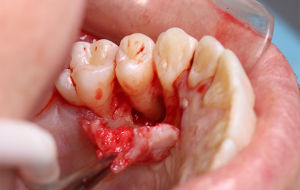

8 e 9 | Acesso palatino e início da enucleação.